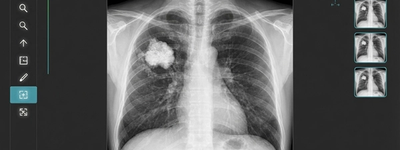

Can an X-Ray Show Cancer in the Bones?

2/16/2026